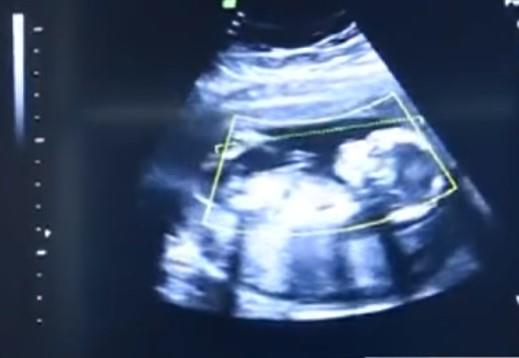

Žena je imala vanmateričnu trudnoću, u kojoj jajna ćelija izlazi iz materice i veže se, najčešće za jajovod, ali u ovom slučaju za unutrašnjost trbušne šupljine, što je stanje opasno po život trudnice i ploda. Nakon što su shvatili o kakvoj je trudnoći reč, doktori su odmah odveli ženu u operacionu salu. Poznato je oko 10 slučajeva kada je beba preživela ovakav tip trudnoće bez ikakvih komplikacija i posledica.

Kod ovakve trudnoće je neophodan carski rez, takođe se mora ukloniti posteljica, što može dovesti do jakog krvarenja kod majke. Kada je hirurg na svet doneo devojčicu, dogodilo se čudo jer, ne samo da je beba bila živa, već nije imala nikakve posledice i bila je teška čak 4 kilograma! Ponosna majka nazvala je devojčicu Veronika, što znači pobeda, a njena priča je postala jako popularna u Rusiji. Nakon ovoga, žena je izjavila da ako ikada ponovo zatrudni, definitivno će redovno posećivati doktora.